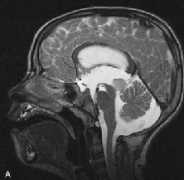

腦干膠質(zhì)瘤有哪些類型?腦干膠質(zhì)瘤(BSGs)是一組組織學(xué)異質(zhì)性腫瘤,主要由它們的位置決定。它們給神經(jīng)外科醫(yī)生帶來(lái)了獨(dú)特的挑戰(zhàn),是一些較難治療的小兒腦腫瘤,需要多學(xué)科的方法...